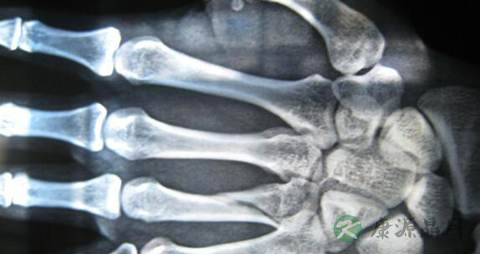

7、人体的钙大部分集中在骨骼里,因此,骨折后,很多人都注重补钙,往往忽略了其他方面的营养补充。骨伤断口要愈合,还需要骨膜和筋腱愈合,需要供血充足才能化瘀和运输营养物质到伤口处,因此,要多吃些富含胶原蛋白和磷元素的食物,贫血者更要注重补血,多吃菠菜等富含铁的食物。